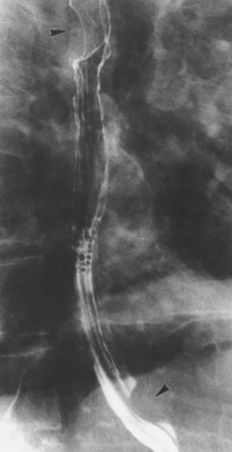

早期中下段食管癌

食管中下段黏膜皱襞局限增粗,中断,箭头所示,管壁僵硬。

早期食管癌